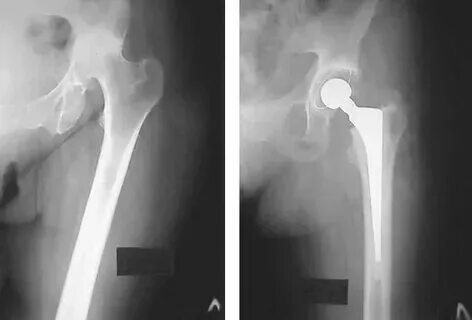

Можно ли мрт после эндопротезирования тазобедренного сустава